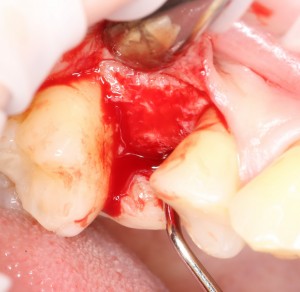

Первое, с чего начинается удаление зуба — это разрез. С помощью скальпеля и периотома отделяется круговая связка зуба. Конкретно в этом случае важно еще увидеть границы лунки, чтобы понять пределы аугментации:

Ну и, зуб проще удалить, если ты видишь, что от него осталось. Что мы и делаем:

Вместе с зубом удаляется прикорневая гранулема. После того, как из лунки удалены все патологически измененные ткани, можно подумать о том, как сохранить объемы альвеолярного гребня в этом участке для будущей имплантации.